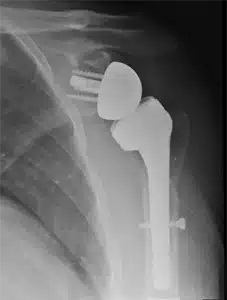

Certain proximal humerus fractures may benefit from surgical intervention, which can be discussed with an orthopedic surgeon who can weigh the advantages and disadvantages compared to non-surgical treatment for your particular injury. Surgery is typically indicated for open fractures (where the bone penetrates the skin) or if the bone is at risk of breaking through the skin, and in cases of shoulder dislocation. Otherwise, surgical intervention is not usually necessary unless deemed appropriate by your medical team. In surgical cases, the surgeon will make an incision over the shoulder, realign the bones, and utilize metal plates and screws for fixation. In instances where the shoulder is severely fragmented and unlikely to heal with conventional repair, shoulder replacement may be recommended as an alternative by the surgeon.

While most proximal humerus fractures do heal, some may fail to do so or may heal in a manner that causes discomfort or restricts movement. Arthritis may develop in some cases, leading to escalating pain and stiffness, irrespective of whether surgery was performed. In older patients experiencing severe pain, shoulder replacement surgery might be recommended. Younger patients may receive advice from their surgeon regarding the removal of hardware or other surgical interventions to address ongoing issues.